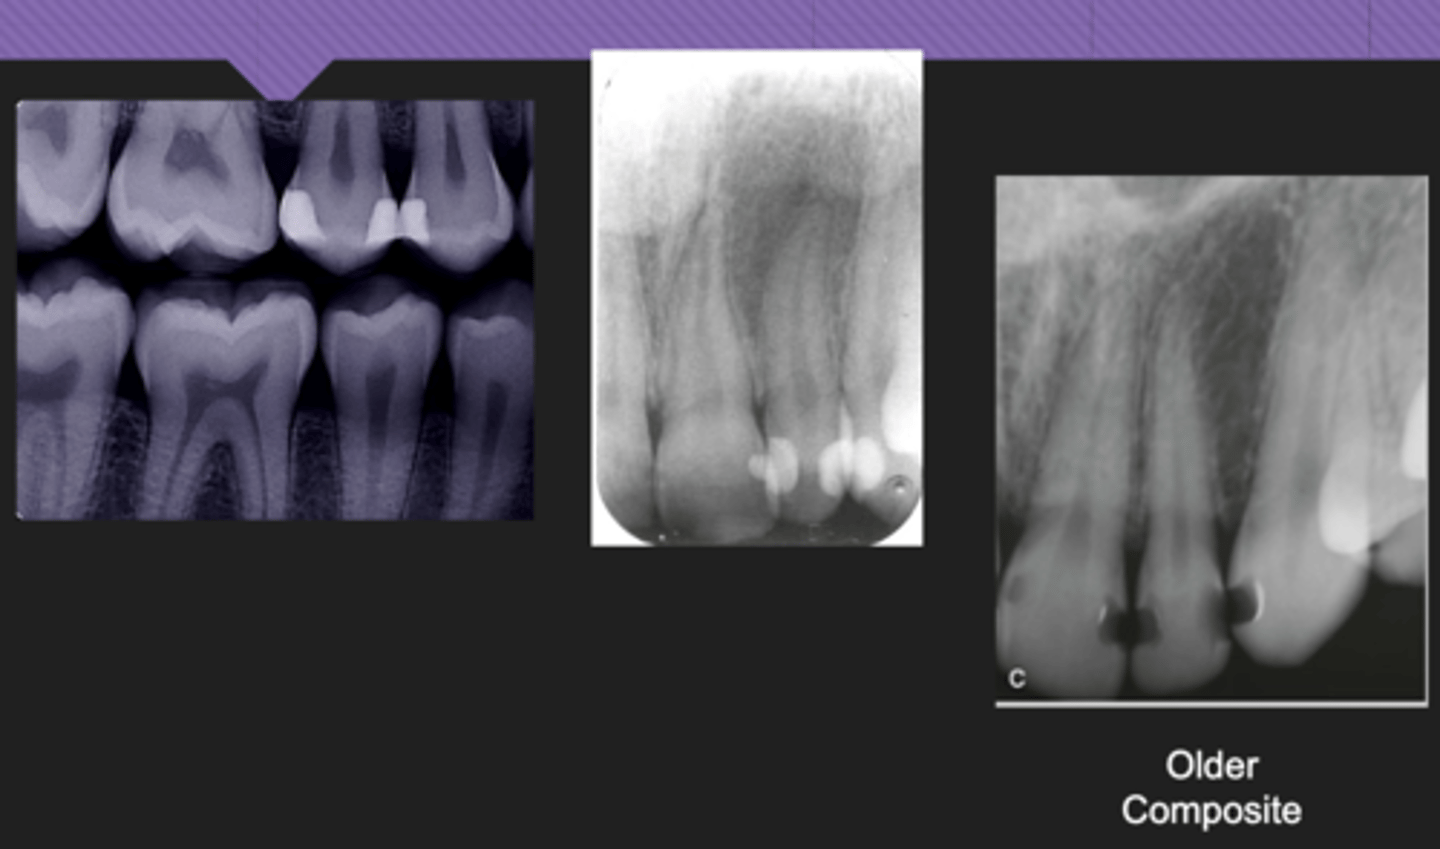

Comosites

- Varying shades of radiolucency depending on material

- Can sometimes mimic decay

- > Older

Composites examples

- Gutta percha: RC filling material

- > Very radiopaque

- Silver points: RC filling material rarely used anymore